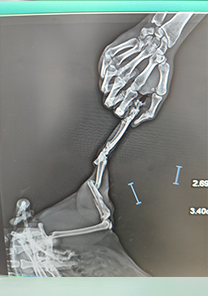

Feyza Hanım'ın Kedisi

Feyza Hanım'ın kedisi, üçüncü kattan düşmeye bağlı olarak femur distalinde kırık yaşamıştır. Femoral cross pin ile fiksasyonu sağlanmış ve Operasyon günü itibarıyla MN - HUND&KATT kullanılmıştır. Operasyonun ardından yürümeye başlayan kedinin pinleri 25 gün sonra çıkarılmış ve tamamen iyileşmiştir.